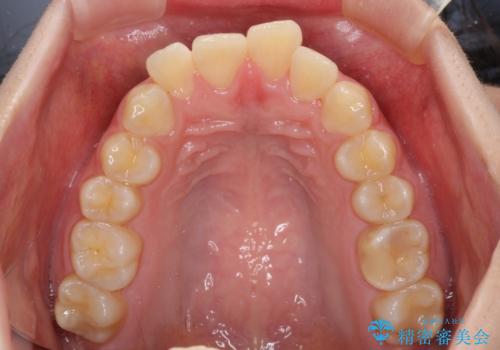

前歯の出っ歯と口の閉じにくさを抜歯矯正で改善 目立たないワイヤー矯正

- 上の前歯の出っ歯とでこぼこの歯並びを気にして来院された患者様です。

口元を積極的に引っ込めるために、上下左右の小臼歯4本を抜歯することとしました。

4本の歯を抜歯したことで、飛び出していた口元が引っ込み、横顔が大きく改善されました。

咬み合わせが悪化することのないようにスペースを閉じていくことができ、比較的スムーズに治療を進めることができました。